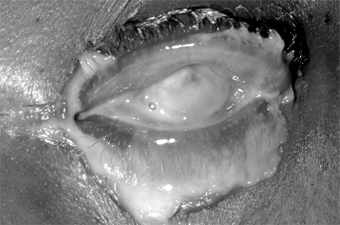

1. Hyperacute (and subacute) bacterial conjunctivitis-Purulent conjunctivitis-

(caused by N gonorrhoeae, Neisseria kochii, and N meningitidis) is marked by a profuse purulent exudate (Figure 5-1). Meningococcal conjunctivitis may occasionally be seen in children. Any severe, profusely exudative conjunctivitis demands immediate laboratory investigation and immediate treatment. If there is any delay, there may be severe corneal damage or loss of the eye, or the conjunctiva could become the portal of entry for either N gonorrhoeae or N meningitidis, leading to septicemia or meningitis.

Figure 5-1: Gonococcal conjunctivitis. Profuse purulent exudate. (Courtesy of L Schwab.)